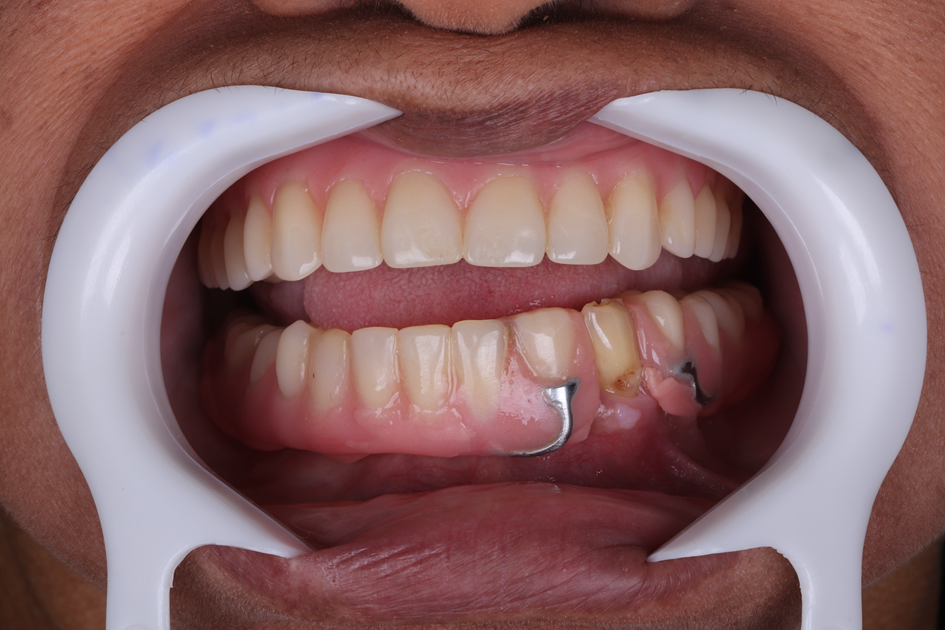

Figura 27 – Foto da prótese protocolo inferior definitiva instalada em boca.

Figura 28 – Foto da prótese protocolo inferior definitiva instalada em boca.